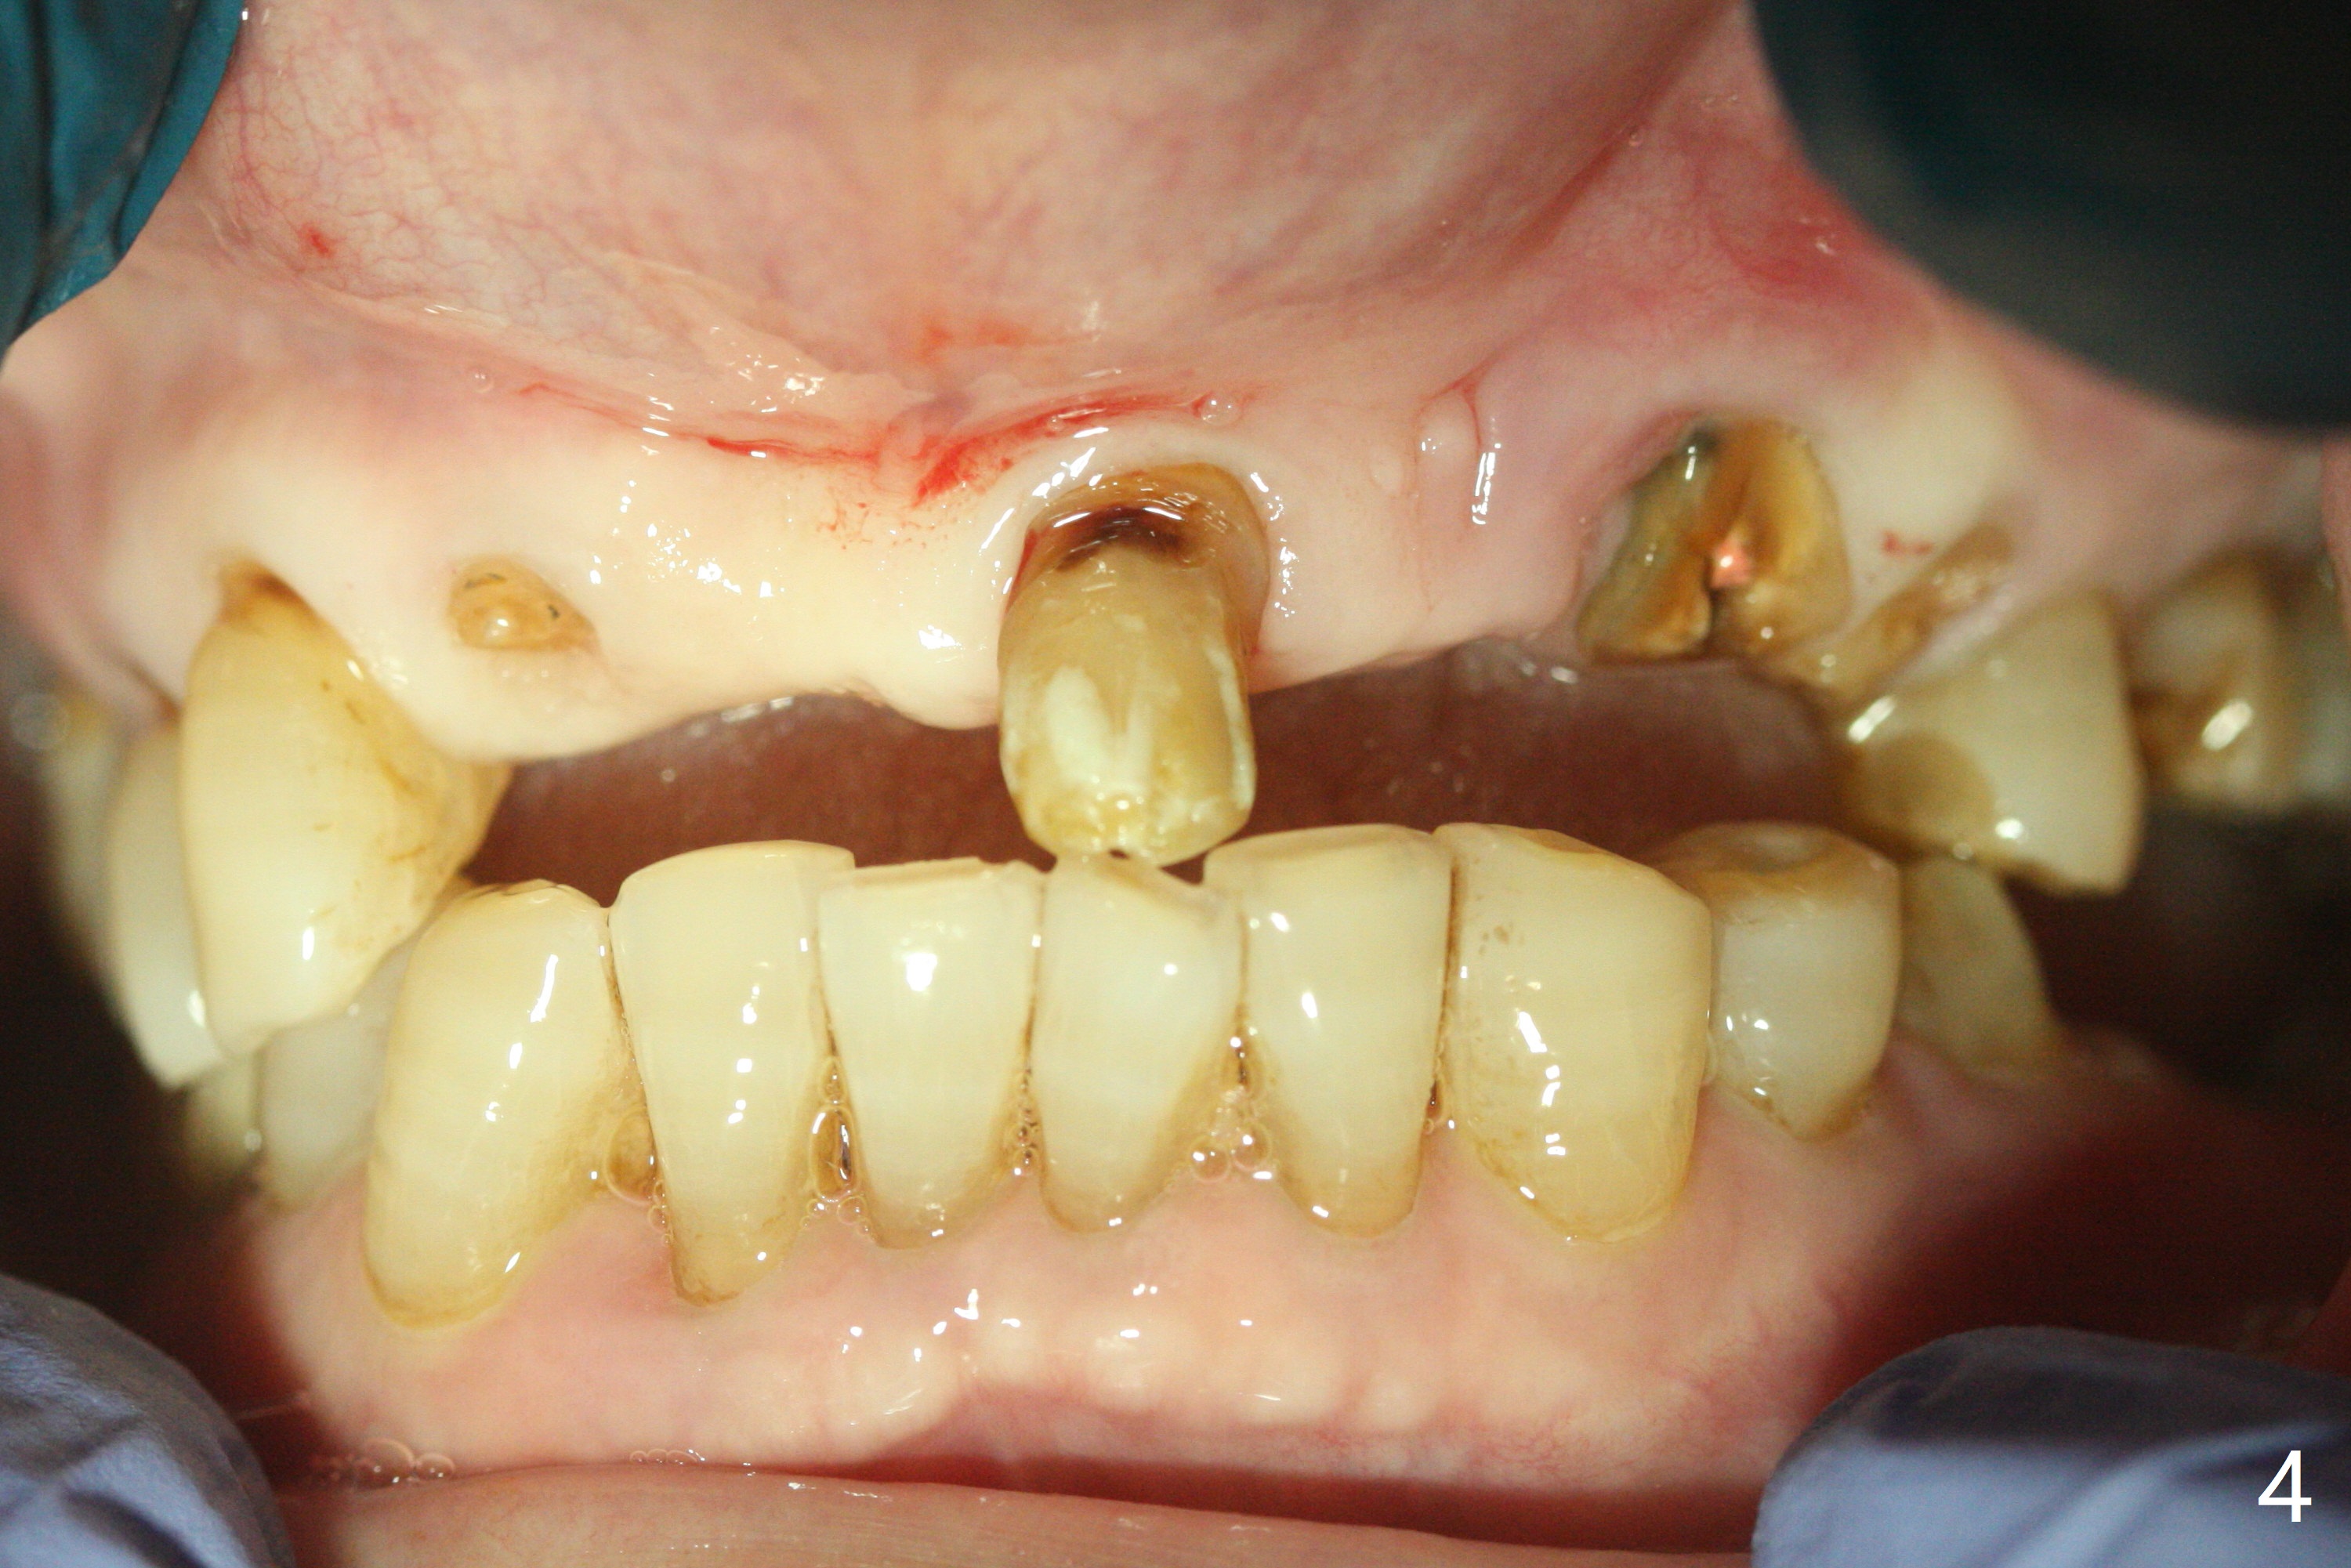

今天下午进入治疗室,粘性骨粉已制备:上清液来自红管(含促凝剂),离心3分钟(图一);再离心10分钟上清液就转变PRF,压制后,使用前剪成三块(图二:黑线),其中两块punch一个洞(图二:圆圈),插入7,9号牙基台固定;大块覆盖11/12号牙牙槽窝(图十四)。7,9,11,12号牙必须拔除(图三),然后在7,9,12种植。由于缺失左下磨牙,前牙垂直距离减少(图四)。完成9号牙位钻洞后,利用fixture mount(图五:M)植入植体,并留在原位固定导板(图六),然后7号牙种植,也留下fixture mount(图六:7,9),最后完成12号牙植入,但是后者扭力低,放置愈合螺帽(图九),而7,9号牙位放置修复基台(图七,八(使用5.5毫米profile drill后),好像基台没有完全就位。7号牙位更换基台似乎没帮助(图十),9号牙位再次放置同一个基台临床上仿佛有改变(比较图八与十二)。放置粘性骨粉后(图十一至十三),牙槽窝口覆盖PRF膜(图十四:P(A:基台)),最后使用树脂敷料固定骨粉和膜(图十五,六),基台帮助敷料固位,没有咬合干扰(图十七:*)。树脂敷料部分解决美观问题,一个月后撤除,如果植体仍有稳定性,可能制作7-10临时牙桥,可能部分维持或者恢复牙龈外形。术后一周病人主诉后面植牙和鼻底疼痛,11号牙根尖牙龈充血(图十八),轻度触痛,可能与术中尚未完全清创有关(图十九(术前CT 3D图像))。再服用Amoxicillin一周,症状好转,鼻底轻度触痛(图二十)。术后1.5月没有任何不适,撤除树脂敷料,7号牙基台(袖)显得太长,换一个短的(4.5x4(5)(图十,十一)->4x4(3)毫米)毫米),植骨好像愈合正常(图二十一:*)。7号牙换了短的基台,9号牙基台高度调整后,与对合牙有足够空间做临时牙桥,最好8,10号牙位牙龈应该凹陷(图二十二:*),有pontic外形。另外9号牙基台颊侧牙龈边缘有所修整,临时牙桥准备。先做7-10临时牙桥,理想临时牙桥pontic处树脂应该多些(图二十三:白线)压迫牙龈形成凹陷。11,12号牙牙槽窝在树脂(Bosworth)敷料下也正常愈合(图二十四)。